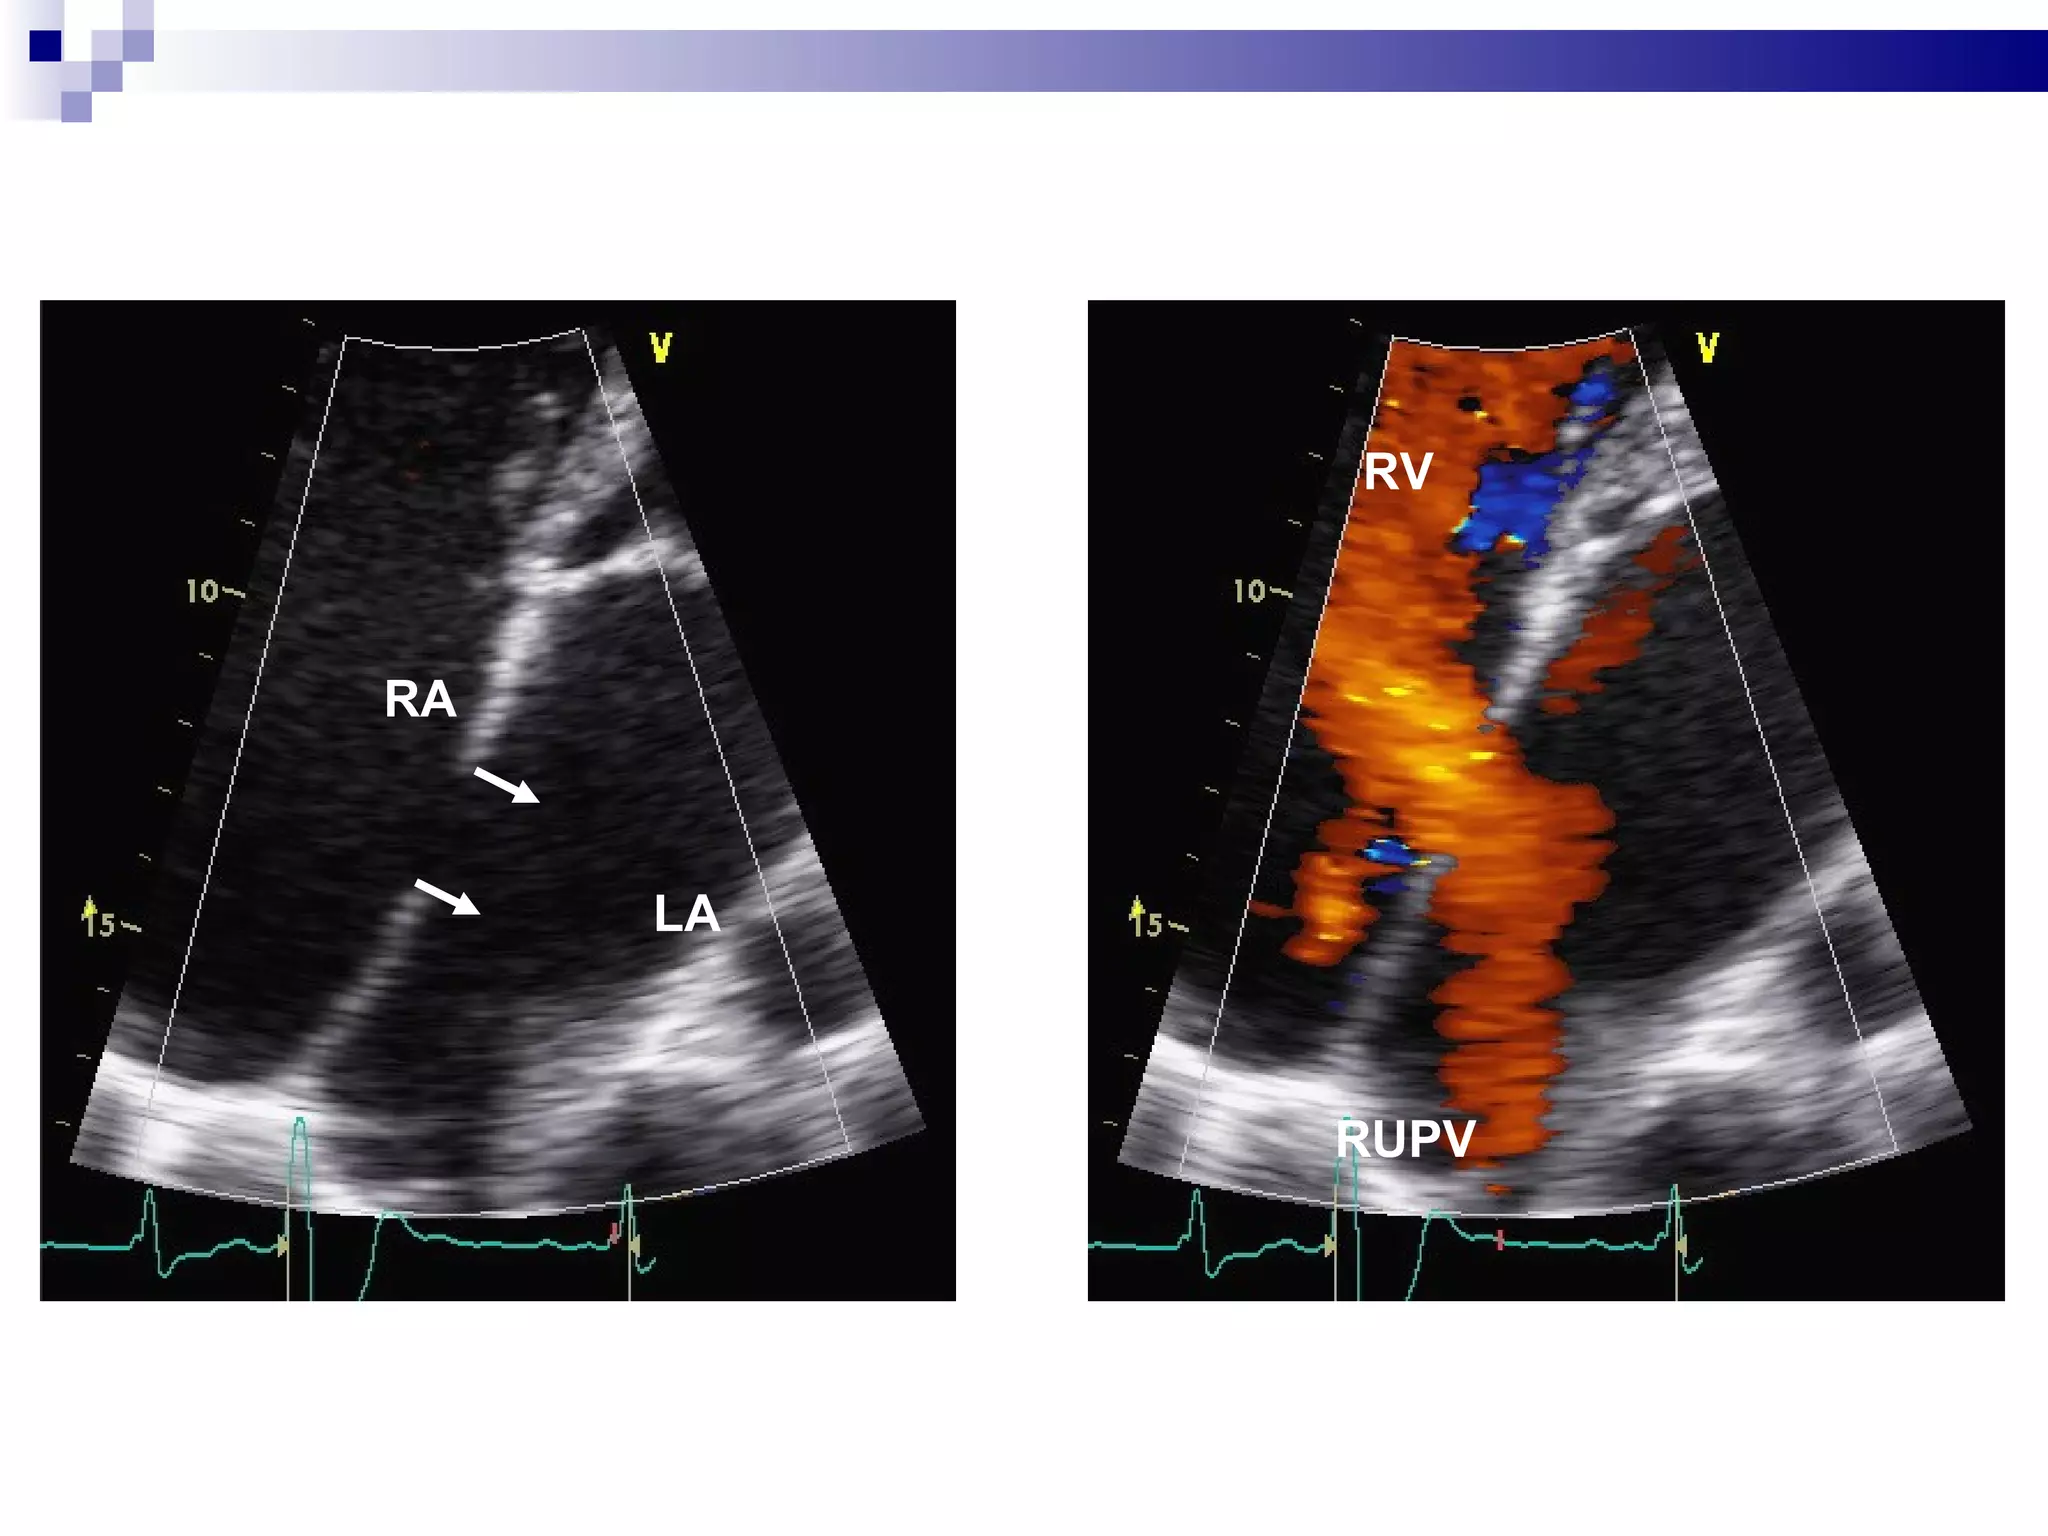

LA RA RUPV RV

LA LA RA RA Fig 9

LA LA RARA Fig 9